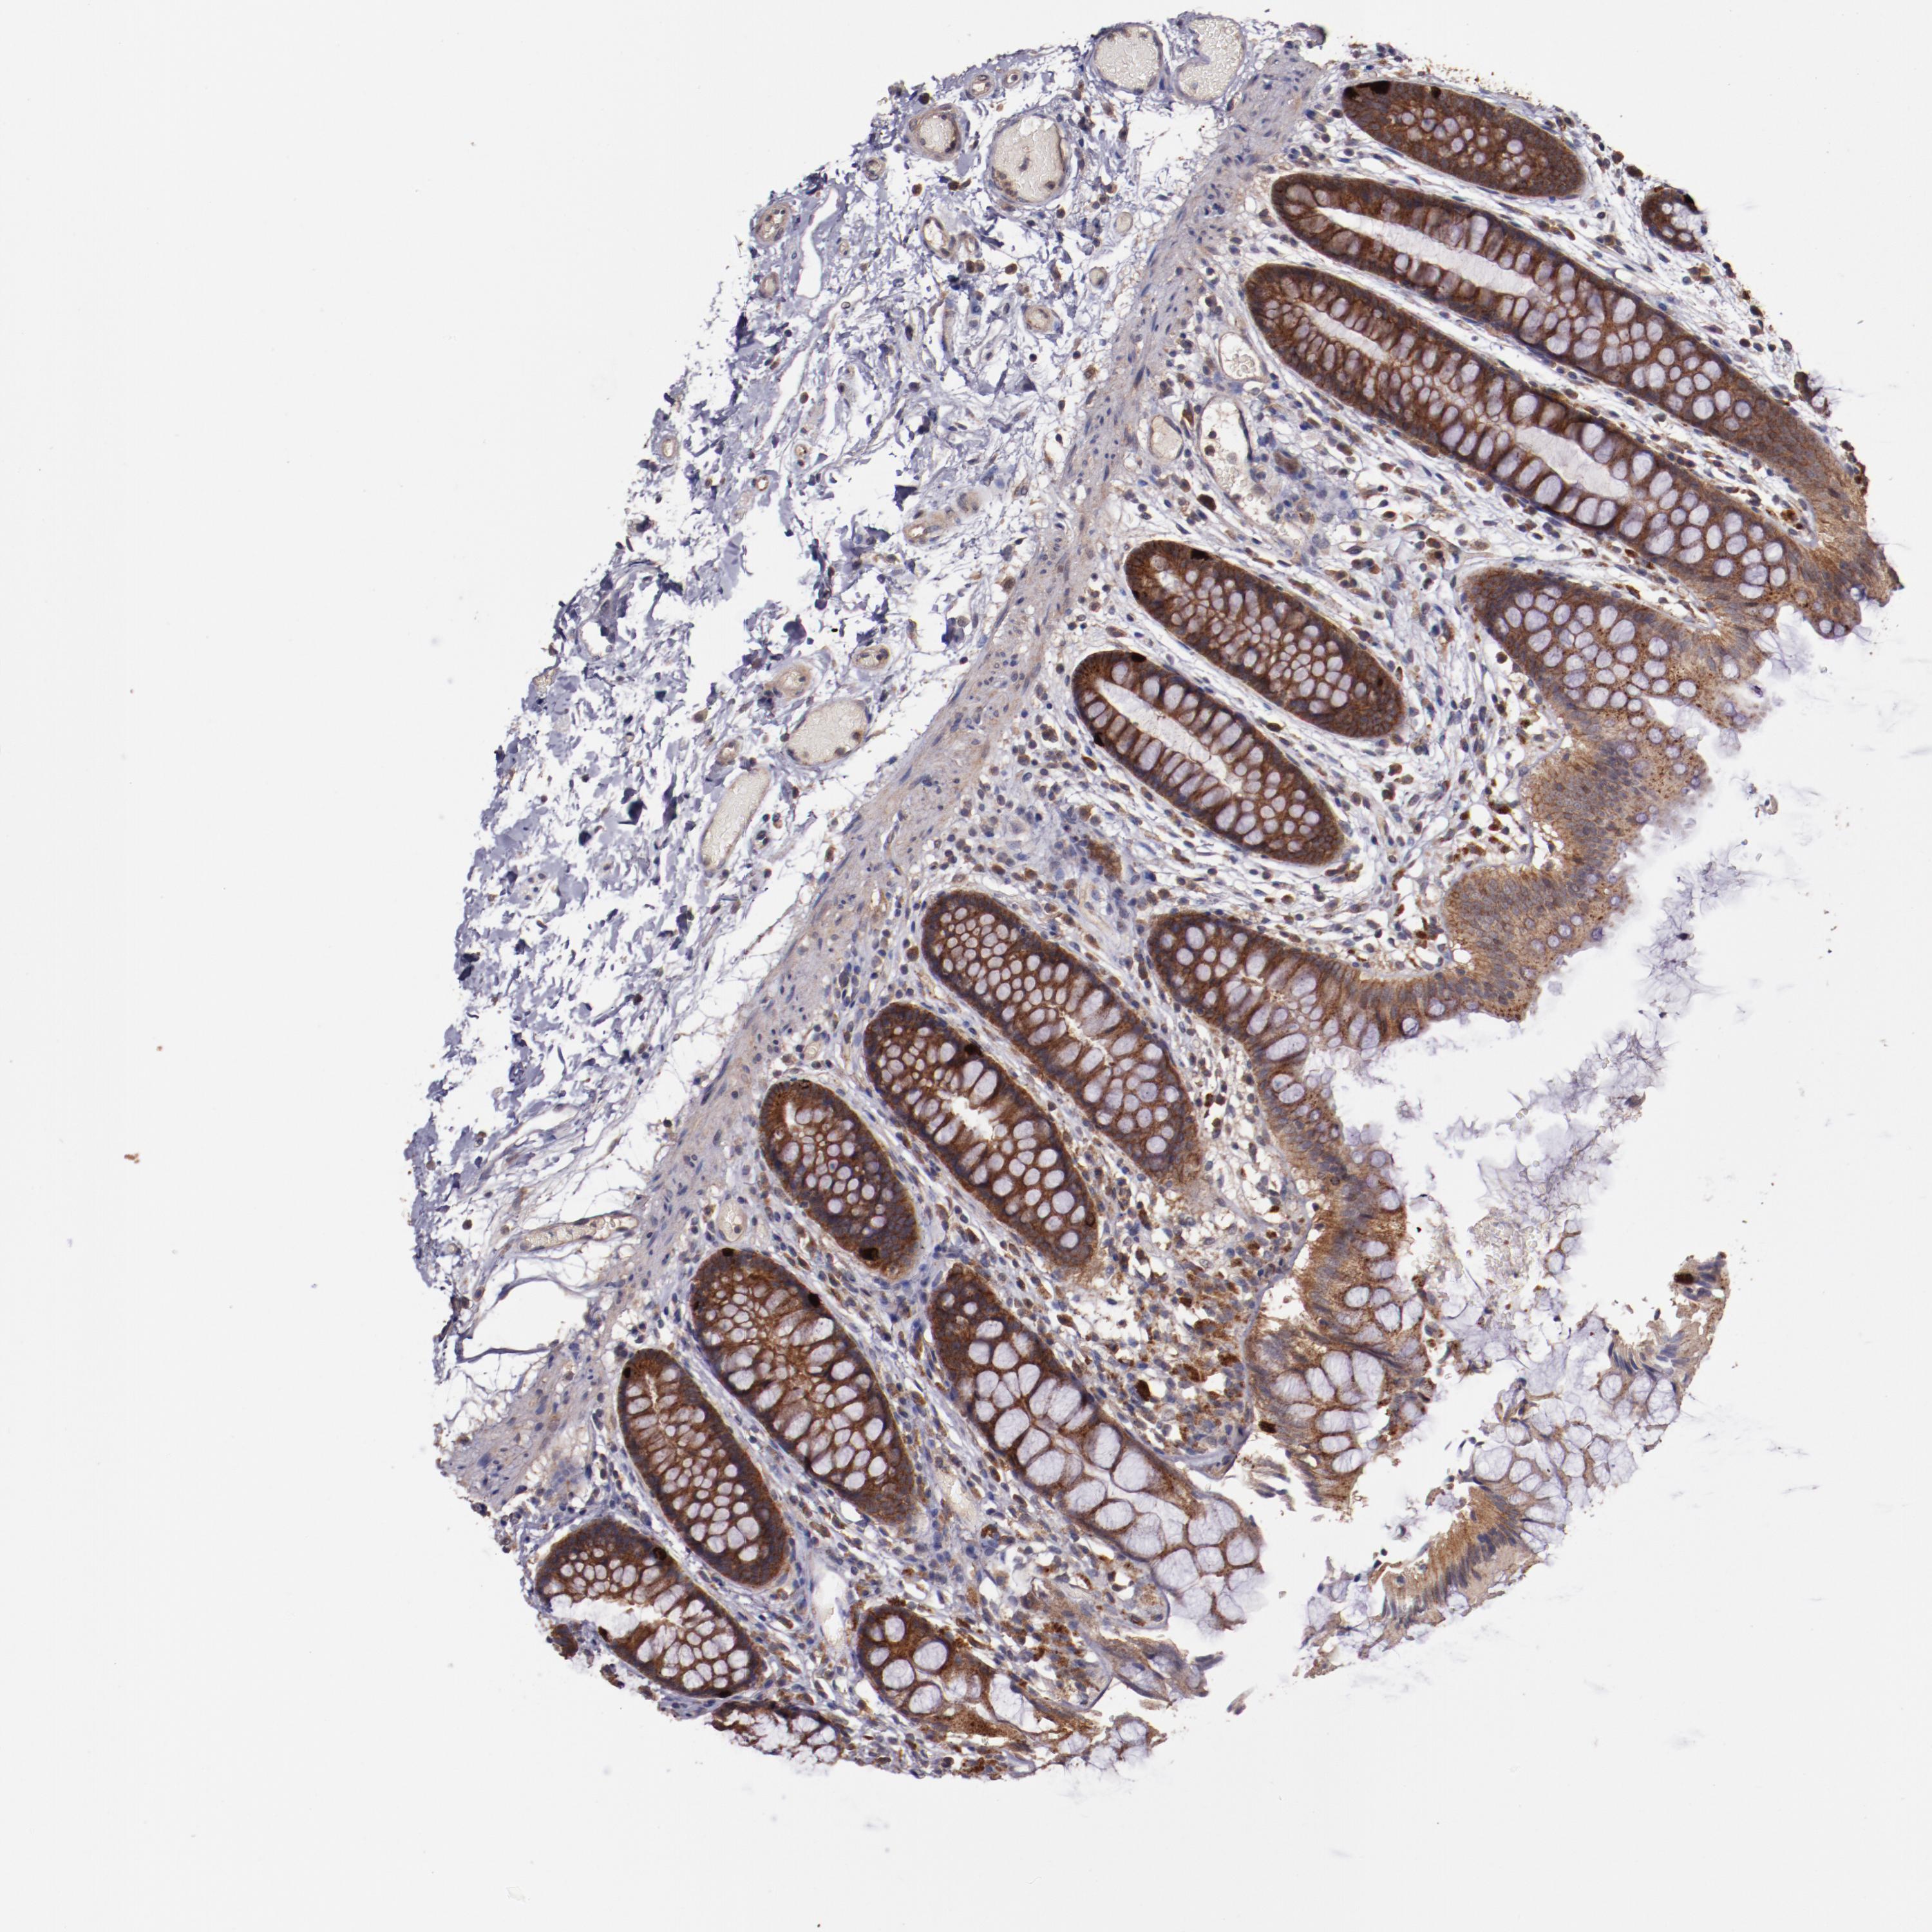

Antibody staining in the annotated cell types in the current human tissue is reported as not detected, low, medium, or high. This score is based on the staining intensity and fraction of stained cells.